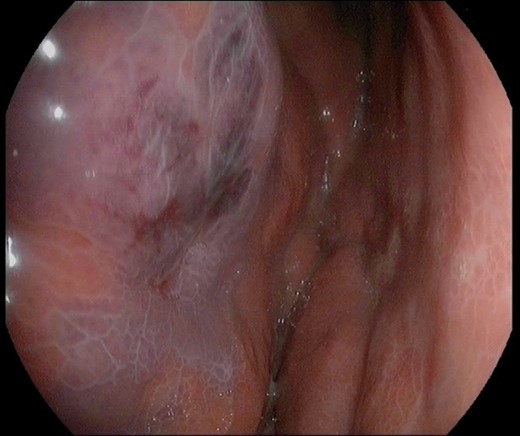

A 45-year-old man presented himself to the emergency department with upper abdominal pain, nausea and vomiting for 3 days. Upon physical examination, the abdomen was tender to palpation but there was no muscle guarding. Laboratory results revealed a high-grade infection, as presented in Table 1. No pneumoperitoneum was seen on the standing chest X-ray. A complementary abdominal CT-scan revealed a widespread thickening of the gastric wall, without signs of perforation (Fig. 1). The patient was admitted and an esophageal-gastro-duodenoscopy revealed diffuse erythema and edema of the gastric wall, suggestive for an acute severe gastritis (Fig. 2). Gastric ischemia or a malignancy, were considered as etiology of the gastritis. H2-blocker and antibiotic therapy with cefuroxime and metronidazole were administered. The next day, the patient deteriorated into a septic shock with multiple organ failure and a high serum lactate (Table 1). A diagnostic laparoscopy was performed. However, due to widespread irreversible gastric ischemia, laparoscopy was converted to a laparotomy (Fig. 3), resulting in a total gastrectomy without primary anastomosis. After surgery the patient was admitted to the intensive care unit for hemodynamic support and continuous veno-venous hemofiltration for multiple organ failure. Because the patient’s condition was considered as unstable, the anastomoses were conducted during a second surgical procedure 2 days after the emergency surgery. During this second surgical procedure a Roux-Y esophagojejunostomy was performed. The overall presentation raised suspicion of streptococcal toxic shock syndrome, causing the multi-organ involvement. This was confirmed when cultures and pathological examination showed a phlegmonous gastritis based on a group A Streptococcus. The patient recovered quickly and 2 weeks after the initial surgery he was discharged.

Image of the gastric mucosa during the esophageal-gastro-duodenoscopy with diffuse erythema and edema of the gastric wall.